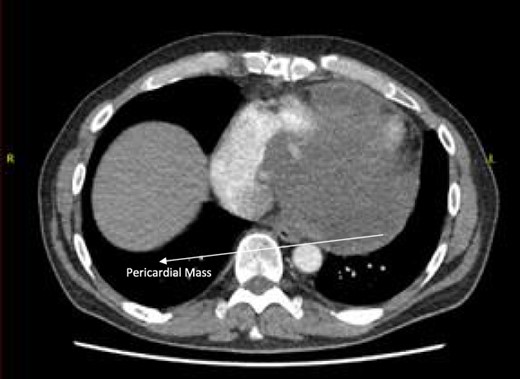

A 52-year-old gentleman was admitted to a district general hospital for shortness of breath causing type 1 respiratory failure with oxygen saturations of <90% despite high flow oxygen. His past medical history was unremarkable, and he was usually fit and well. A CT Pulmonary Angiogram (CTPA) was undertaken, which showed a heterogeneous oval-shaped lesion measuring 15 × 9 × 14 cm3 between the heart and the diaphragm, with a median attenuation of 35 HU and no enhancement during the arterial phase. Further solid lesions of 14 mm in the right lower lobe and 5 mm in the right upper lobe raised the suspicion of a primary cardiac sarcoma with pulmonary metastasis. This is shown in Fig. 1. Subsequent urgent CT staging (Fig. 2) was undertaken, which confirmed an indeterminate space occupying the inferior pericardial space, right atrial (RA) filling defect and anterior nodular pericardial thickening. No intra-abdominal or bone lesions were identified. An echocardiogram also confirmed these finding with the addition of no flow through the tricuspid valve (TV), as shown in Fig. 3.

CT thorax-abdomen pelvis, depicting the RA filling defect as well as pericardial bulk.

Follow-up CT scans were undertaken during chemotherapy that showed continued reduction in the size of the RA tumour, as demonstrated in Figs 4 and 5. The pericardial mass following chemotherapy is visualized in Fig. 6.

Post-operative CT scan showing pericardial mass following chemotherapy.